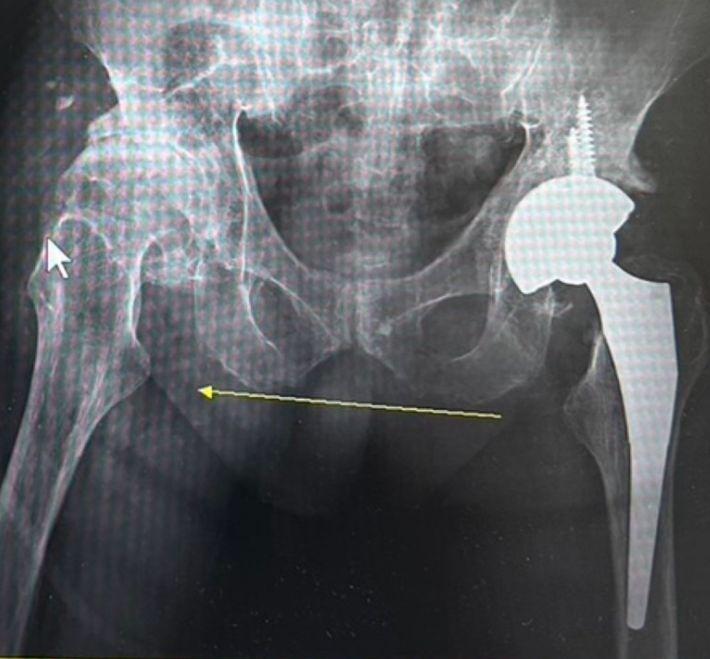

The Complete Guide to Minimally Invasive Hip Replacement Surgery: Smaller Incision, Rehab-Free Recovery, Regain Your Stride

Hip joint pain making walking difficult and squatting impossible? Dr. Chien-Chun Chang explains "Minimally Invasive Total Hip Arthroplasty." This guide details how the Direct Anterior Approach (DAA) and innovative Anterior-Lateral Muscle-Sparing techniques achieve muscle preservation, allowing patients to walk on the same day after surgery. It includes a comparison of artificial joint materials, recommended out-of-pocket cost estimates, and a postoperative recovery guide to help you make a precise evaluation and regain your mobility.